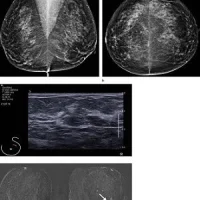

A research team from the Eindhoven University of Technology has recently developed a contrast-enhanced, ultrasound imaging method, which enables dynamic contrast specific ultrasound tomography (DCS-UST), in order to offer a breast-friendly and safer alternative to mammography.

The regular screening method for detecting breast cancer, the mammogram, is unpleasant, as it requires the breast to be squeezed tight. Moreover, it can be a contributor to the onset of cancer. More than two-thirds of the cases where a worrying anomaly is found on the X-ray images are false positives. Scientists thus seek alternatives in order to reduce or even eliminate such issues. Libertario Demi and colleagues, of UT Eindhoven, have developed a new technology in which the patient lies on a table and the breast hangs freely in a bowl. The method is known as ‘cumulative phase delay imaging (CPDI)’ and uses special echography, i.e. inaudible sound waves, to create a 3D image of the breast. The researchers expect that the rates of false positives will be much lower, as the technique generates images in which any tumour is clearly identifiable.

CPDI will lead to “a more practical, faster, and less operator-dependent imaging procedure compared to standard echo-contrast, while preserving accurate imaging of contrast kinetics.” Moreover, it can find clinical applications as a diagnostic method for breast cancer localisation. The researchers are planning to start performing preclinical studies once they put together an international, expert medical team. Application of the new technique is estimated to be ten years away. It is also expected that the new technology will probably operate in combination with other methods. The team’s future work will focus on “taking new measurements with a breast ultrasound computed tomography scanner on heterogeneous and more complex flow-phantoms, with the ultimate aim of transferring our technology to patients.”